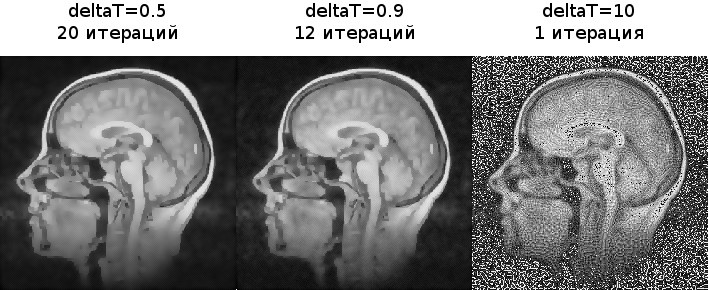

Крайнее левое изображение — оригинальное, справа от оригинального — фильтрованные с различными параметрами.

Посмотрим как поведет себя алгоритм для разных шагов по времени (t=10,k=5).

Изображения получились практически идентичные. Теперь попробуем нарушить условие устойчивости.

Как мы видим, при небольших отклонениях некоторое размытие еще происходит, но начинают появляться артефакты. При deltaT=10 они уже заполняют все изображение.